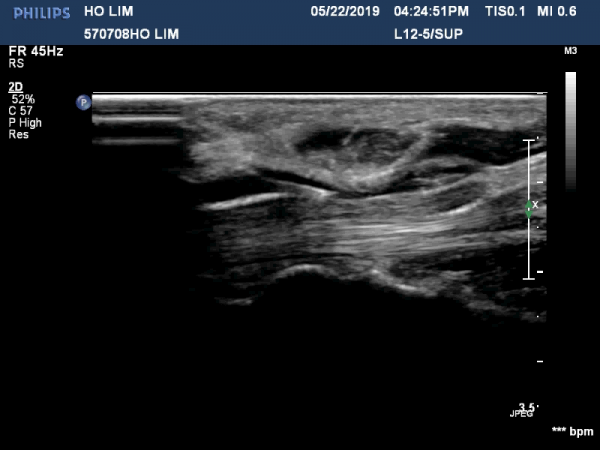

¼ö±Ù°ü ¸»´ÜºÎÀ§(trapezium, capitate level)¿¡¼ Á¤Á߽Űæ Ⱦ´Ü¸é°Ë»ç»ó Á¤Á߽ŰßÀÇ ÆíÆòȰ¡ °üÂûµÊ(»çÁø 3).